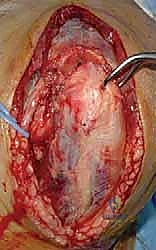

2. النهج الجراحي (Surgical Approach) والتعامل مع العصب الزندي

يستخدم الدكتور هطيف النهج الخلفي للكوع (Posterior Approach). الخطوة الأولى والأهم بمجرد فتح الأنسجة هي تحديد العصب الزندي. يتم عزل العصب بعناية فائقة باستخدام أشرطة مطاطية واقية. اعتماداً على نمط الكسر وموقع الشرائح التي سيتم وضعها، قد يقرر الجراح ترك العصب في مكانه أو نقله إلى الجزء الأمامي من الكوع (Anterior Transposition) لحمايته من الاحتكاك الميكانيكي بالمعدن مستقبلاً.

3. كشف المفصل (Joint Exposure)

للوصول إلى السطح المفصلي المعقد لعظم العضد، هناك عدة طرق. الطريقة الأكثر شيوعاً والتي توفر أفضل رؤية هي قطع الناتئ الزندي (Olecranon Osteotomy). في هذه التقنية، يقوم الجراح بعمل قطع دقيق في شكل حرف V في عظم الكوع (الزند) لقلب وتر العضلة ثلاثية الرؤوس (Triceps) للأعلى، مما يكشف مفصل العضد بالكامل.

في حالات أخرى أقل تعقيداً، قد يستخدم الدكتور هطيف تقنيات تحافظ على العضلة ثلاثية الرؤوس (Triceps-sparing approaches) لتقليل وقت التعافي.

4. الرد المفتوح (Open Reduction) - إعادة تجميع القطع

هنا تبدأ المرحلة الهندسية الدقيقة. يقوم الجراح بتنظيف موقع الكسر من الجلطات الدموية والأنسجة الميتة. ثم يبدأ في إعادة تجميع الشظايا العظمية (كأنها قطع أحجية/بازل). يتم التركيز أولاً على إعادة بناء السطح المفصلي (البكرة والرأس) بدقة تشريحية تامة بنسبة 100% لتجنب خشونة المفصل مستقبلاً. يتم تثبيت هذه القطع مؤقتاً باستخدام أسلاك كيرشنر (K-wires) الدقيقة.

يتم غسل الجرح جيداً بمحاليل معقمة، ويتم وضع أنبوب تصريف (Drain) لمنع تجمع الدم، ثم تُخاط الأنسجة والجلد بعناية فائقة لتقليل الندبات (بفضل خبرة الدكتور هطيف في الجراحة الميكروسكوبية التجميلية). وتوضع جبيرة خلفية خفيفة.